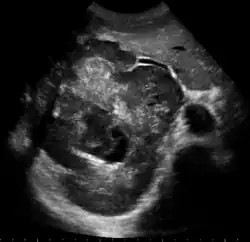

Large HCC filling almost entire of right lobe